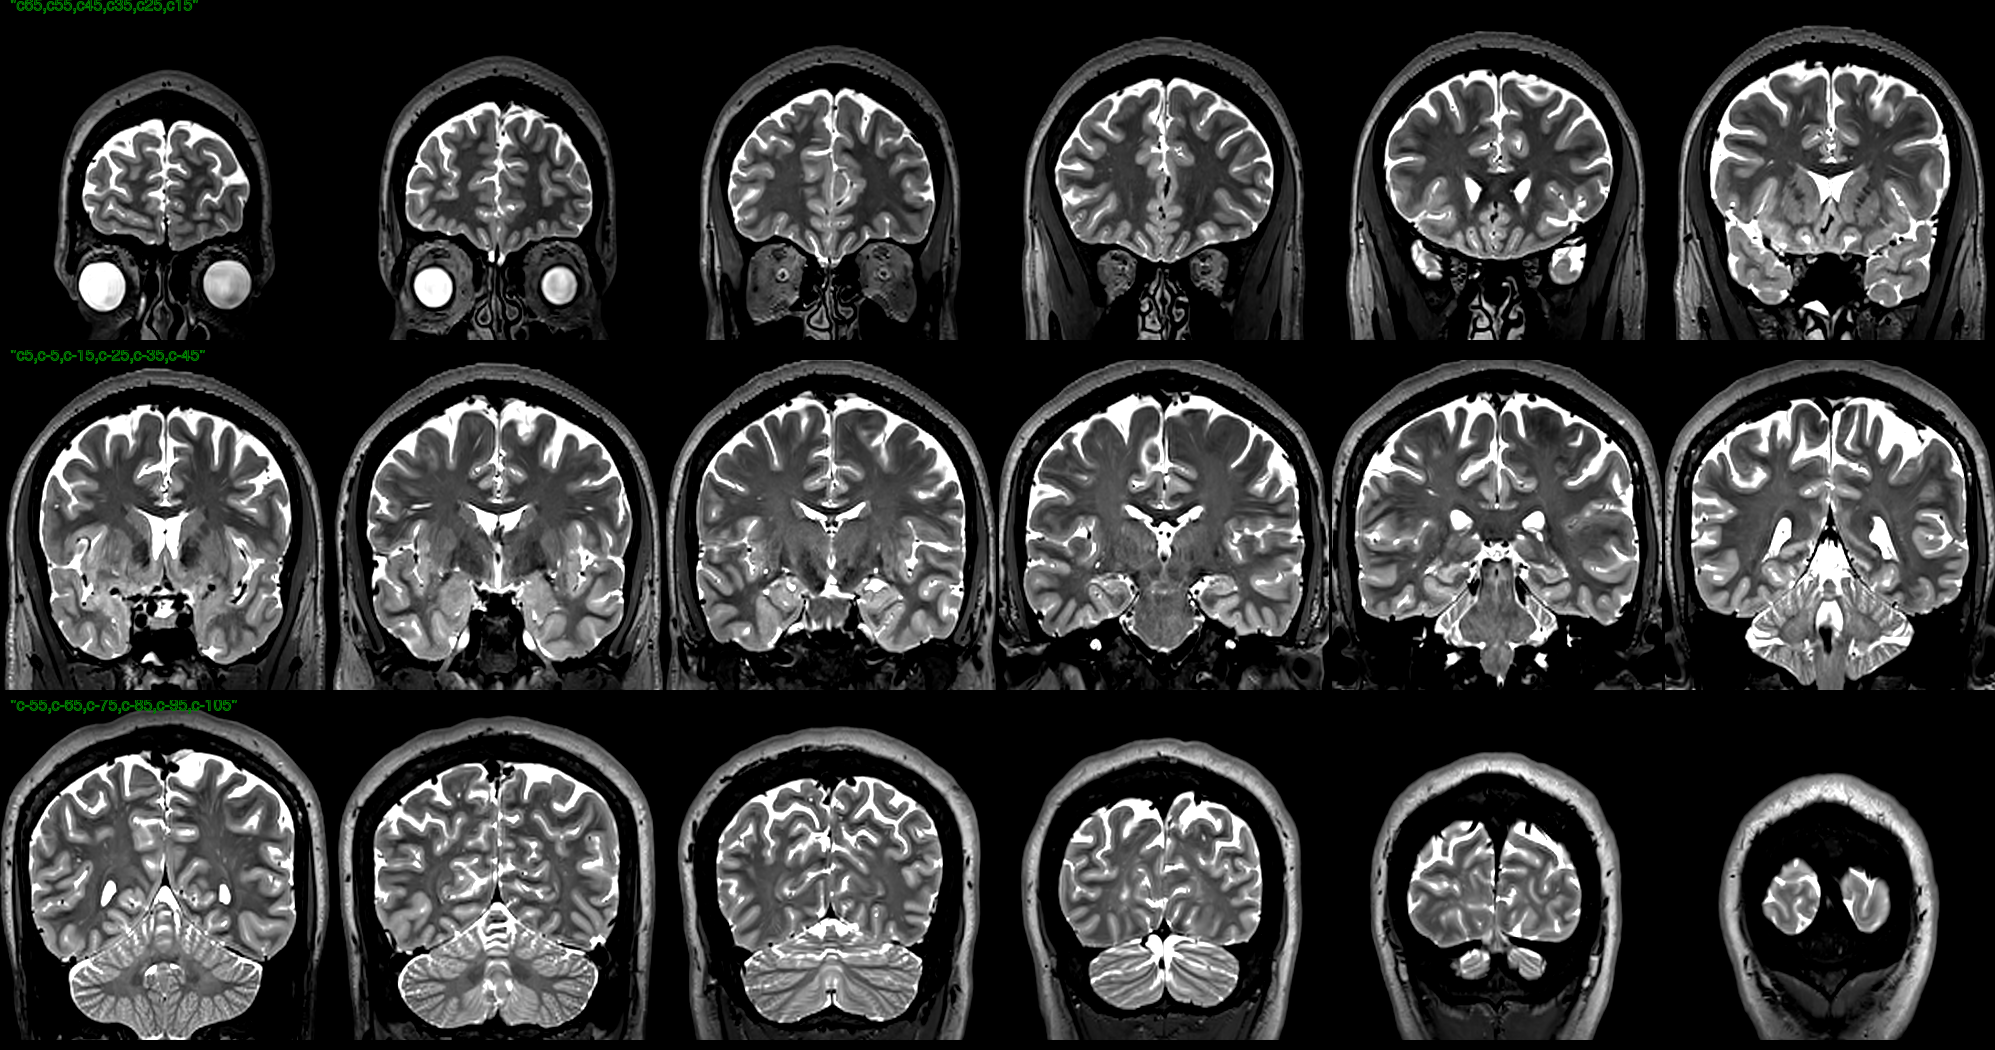

T2 images